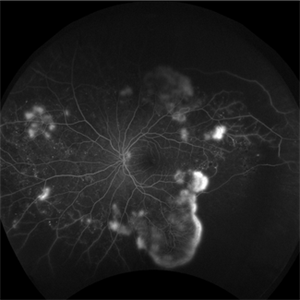

Proliferative Diabetic Retinopathy

Jul 11 2018 by Sarah Oelrich

Proliferative diabetic retinopathy.

Photographer: Sarah Oelrich CRA, Southeastern Retina Associates, Knoxville TN

Imaging device: Optos 200tx

Condition/keywords: proliferative diabetic retinopathy (PDR)